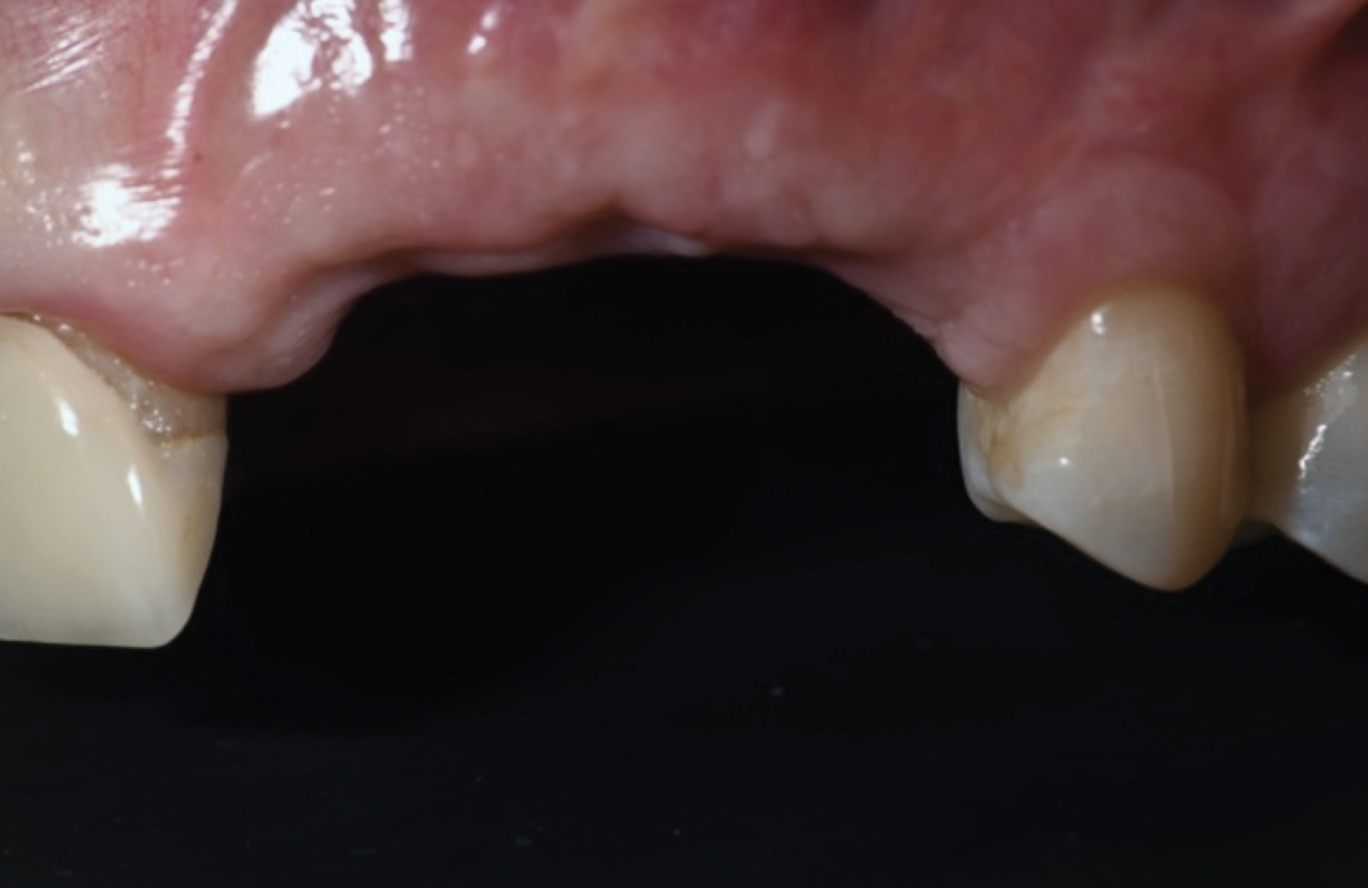

Fig 13. Distortion of the mucogingival junction.

Figure 13

This approach was effective in increasing the horizontal and vertical soft-tissue thickness around the three implants. Nevertheless, a distortion of the MGJ was still present (Figure 13). Therefore, 3 months after the iCTG augmentation, it was decided to perform a second soft-tissue augmentation procedure with the goal of repositioning the MGJ in an adequate level on the buccal aspect, increasing the width of the keratinized mucosa at the implant sites. A modified apically positioned flap was performed (Figure 14). Two labial strip gingival grafts were harvested from the anterior mandible and maxilla and sutured onto the recipient bed with a 7-0 polyglycolic acid resorbable suture.5,17,18 The residual periostium was covered with a non-crosslinked xenogeneic collagen matrix (Figure 15).

One of the main endpoints of implant therapy in the anterior region is patient satisfaction, and this can be highly dependent on the level of the peri-implant soft-tissue margin and the height of the peri-implant papillae.7,8,19 The bone augmentation procedures provided an adequate bone volume and height that enabled the placement of the three dental implants in ideal prosthetically and biologically driven positions. These procedures, however, often result in displacement of the MGJ.5,15,17,18 The first soft-tissue augmentation surgery aimed at increasing soft-tissue thickness in a horizontal and vertical aspect.7,12,20 The iCTG augmentation technique involved augmentation of mucosal thickness on the buccal aspect, which has been demonstrated to have beneficial effects on marginal bone level stability over time,20,21 and augmentation of the interproximal soft tissue, which can result in higher and thicker peri-implant papillae.3,4,10,22 This augmentation procedure requires closure by primary intention to maximize the gain in supracrestal tissue height, and therefore the distortion of the MGJ cannot be corrected with this bilaminar approach. The second soft-tissue augmentation surgery involves an apically positioned flap in combination with two labial strip gingival grafts.5,18 The primary goal of this procedure was in this case to reposition the MGJ on the buccal aspect, increasing keratinized mucosa width at the implant sites.5,18